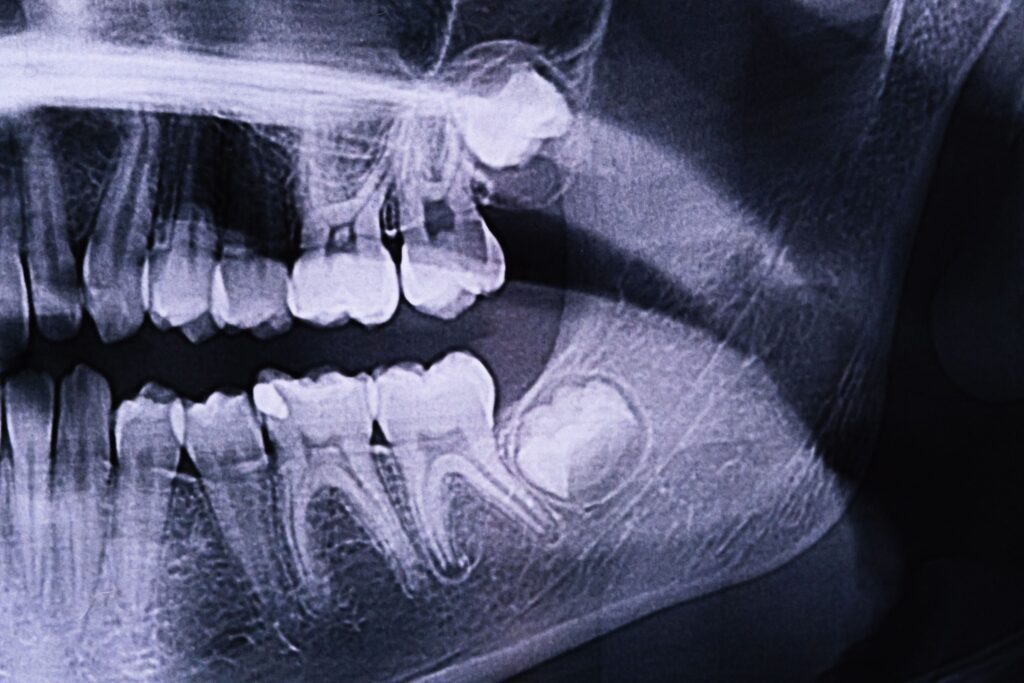

Διαγνωστικές μέθοδοι

Η επίσκεψη στον οδοντίατρο είναι απαραίτητη για τη διάγνωση. Οι μέθοδοι περιλαμβάνουν:

- Κλινική εξέταση: Οπτικός έλεγχος της στοματικής κοιλότητας.

- Ακτινογραφίες: Πανοραμικές ή τρισδιάστατες απεικονίσεις για εντοπισμό του δοντιού.

- Ορθοδοντική αξιολόγηση: Για τον σχεδιασμό πιθανής θεραπείας.

Τα έγκλειστα δόντια δεν είναι πάντα εμφανή, γι’ αυτό οι τακτικοί οδοντιατρικοί έλεγχοι είναι απαραίτητοι για την υγεία του παιδιού.